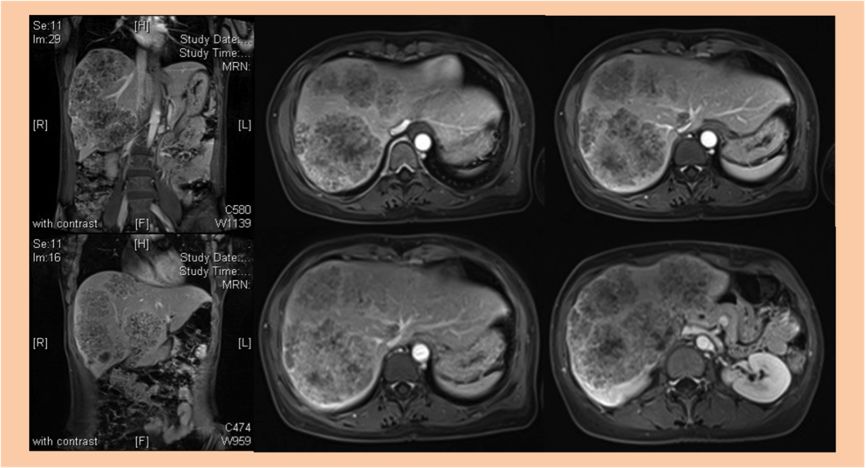

2017-11-03 肝脏MR增强:肝右叶及左内叶见多发团状异常信号影,较大者位于V及VI段,大小约13*7cm,病灶信号不均。增强后病灶呈边缘强化。肝IV段另可见一类圆形长T1长T2信号影,大小约2.9*1.9cm。考虑转移瘤。

1. 该患者诊断为结肠癌伴多发性肝转移,肝脏MR增强示肝右叶及左内叶可见多发团状异常信号影,考虑为转移瘤。较大者位于V及VI段,大小约13*7cm,肿瘤病灶大,负担重,转移瘤肝转移灶初始不可切除

2. 考虑患者情况,首先选择FOLFIRI+西妥昔单抗(爱必妥)方案进行转化治疗,每2周一次,治疗8周期后,转化治疗疗效显著,肝转移灶部分缓解,肝脏转移灶转化治疗后由原先的不可切除变为可切除